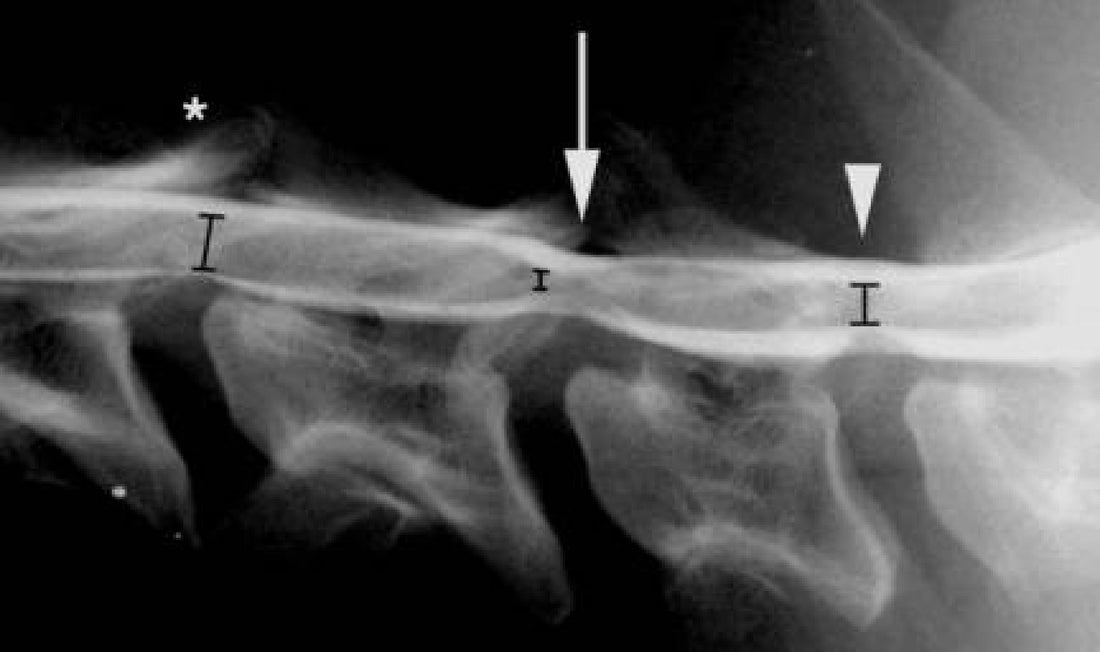

Για τη συγκεκριμένη διάγνωση της νόσου πρέπει να κάνουμε κάποιες απεικονιστικές εξετάσεις. Συνήθως κάνουμε πρώτα ακτινογραφίες για να δούμε αν μπορούμε να αναγνωρίσουμε οποιαδήποτε προφανή οστική βλάβη ή να διαγνώσουμε άλλες ασθένειες που μπορούν να μιμηθούν το σύνδρομο Wobbler. Για την επιβεβαίωση της νόσου απαιτούνται πιο προηγμένες απεικονιστικές εξετάσεις. Παλαιότερα κάναμε μυελογράμματα (ακτινογραφία με έγχυση βαφής γύρω από το νωτιαίο μυελό). Αυτή η τεχνική χρησιμοποιείται σπάνια στις μέρες μας γιατί υπάρχουν καλύτερα, πιο ευαίσθητα τεστ. Η καλύτερη εξέταση είναι η μαγνητική τομογραφία (όταν συγκρίναμε μυελόγραμμα και μαγνητική τομογραφία κατά μέτωπο είδαμε ότι η μαγνητική τομογραφία ήταν σαφώς ανώτερη). Η μαγνητική τομογραφία είναι επίσης πολύ ασφαλής. Δεν βλέπουμε καμία νευρολογική επιδείνωση μετά από μαγνητική τομογραφία, ενώ αυτό συνέβαινε συχνά με μυελογραφήματα (συνήθως η επιδείνωση ήταν ήπια και παροδική). Η αξονική τομογραφία (αξονική τομογραφία) είναι επίσης μια καλή εξέταση, αλλά πιθανώς όχι τόσο καλή όσο η μαγνητική τομογραφία. Συνήθως αυτές οι εξετάσεις γίνονται από ειδικούς σε μεγαλύτερα Νοσοκομεία ή εξειδικευμένες κλινικές.